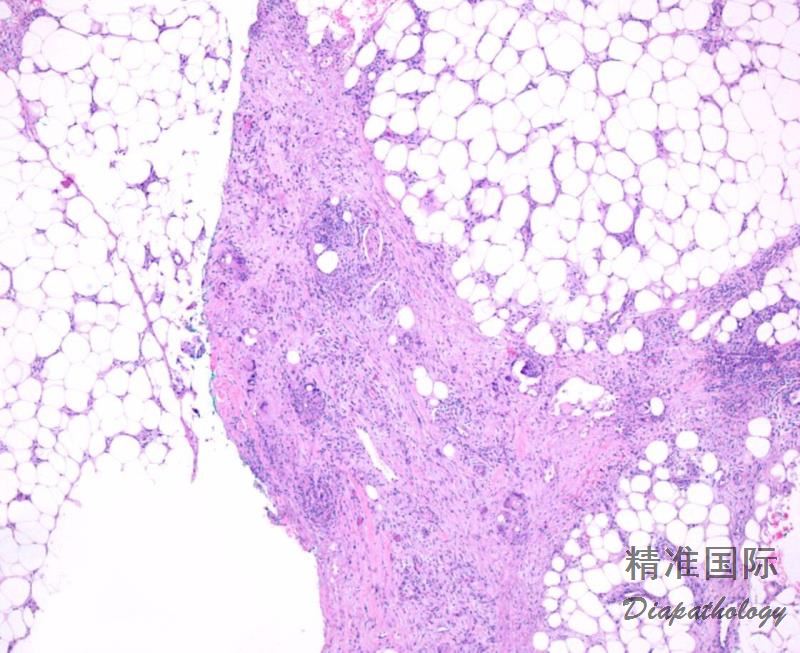

1. 间隔性脂膜炎的典型代表。

2. 早期主要是小叶间隔的炎症反应, 以淋巴细胞、组织细胞浸润为主。 也可以有少量中性粒细胞和嗜酸性粒细胞。炎症反应常延伸至间隔周围的脂肪小叶, 出现间隔性脂膜炎和小叶性脂膜炎的混合表现。

3. 后期在间隔中会有肉芽肿形成。 最终间隔纤维化。